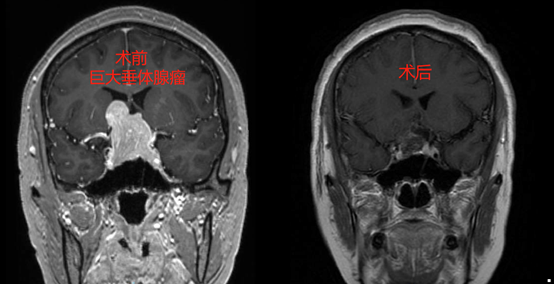

看看我们近期收治的几例良性肿瘤患者,您还敢不做颅脑的体检嘛?

7.闭经泌乳,不孕不育。育龄妇女非妊娠的闭经、泌乳常为垂体肿瘤的首发症状。男性主要表现为阳痿和阴毛、腋毛、胡须脱落、皮肤细腻等。出现上述症状不要只就诊于妇科或男科哟,说不准是大脑的事儿呢。

8.肥胖、肢端肥大、样貌变丑、不明原因的三高、睡眠呼吸暂停。这也可能是垂体瘤的首发症状。